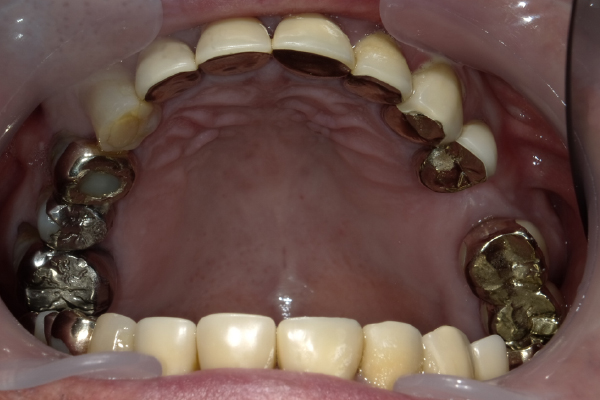

Case12

| 主訴 | 左右の歯が無い所にインプラントして欲しい |

|---|---|

| 治療期間 | 約3か月 |

| 治療費 | 1,050,000円 |

| 治療内容 | 左右の奥歯が無かったので、患者様と相談し、右上にはノンクラスプデンチャー(バネが見えない入れ歯)、左側にはインプラントを2本入れ、ブリッジという構造で上物を3本分入りました。今までとは全く食べれるものが変わって大変喜んでおられました。 |

| 治療の リスク | インプラントも残っている歯と同様に歯周病になる可能性がある |